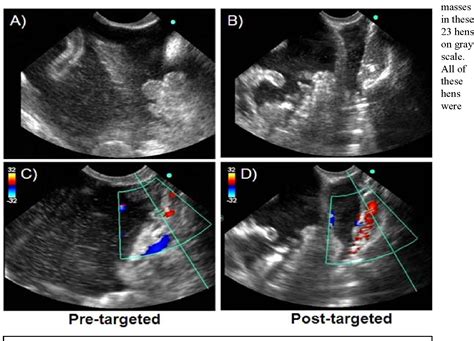

• Blood Flow: Doppler ultrasound can assess blood flow to the ovaries, which is essential for their proper functioning.

• Follicular Development: The presence of developing follicles, especially during the follicular phase of the menstrual cycle.

• Corpus Luteum: The formation of the corpus luteum after ovulation, which produces progesterone to support the lining of the uterus.